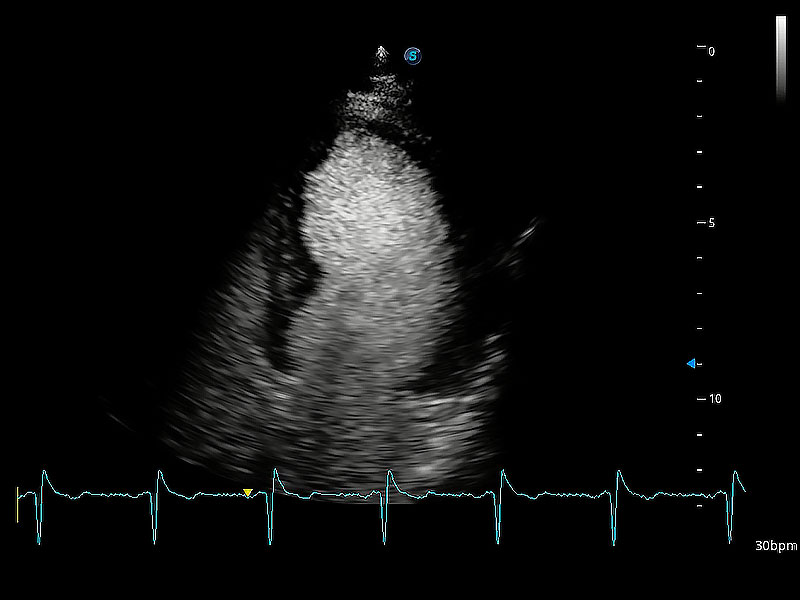

ProPet 80 配備了豐富的心臟探頭群、先進(jìn)的成像技術(shù)和專業(yè)的心臟測(cè)量工具,可幫助動(dòng)物醫(yī)生為不同體型和生理結(jié)構(gòu)的動(dòng)物提供心臟和心肌功能的全面評(píng)估。

能夠增加心肌組織與血流之間的區(qū)別。對(duì)于心臟掃查困難的動(dòng)物,可提供更好的心內(nèi)膜邊界的顯示。